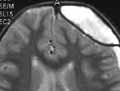

Посттравматическая внутричерепная пневмоцефалия (Таблица 4).

В 74% случаев — как результат ЧМТ. Встречается в 3% всех переломов основания черепа; в 8% костей черепа с заинтересованностью околоносовых пазух. В 25% случаев выявляется сразу после черепно-мозговой травмы, обычно на 4-5 день. Иногда сохраняется до 6 месяцев (в 33%).